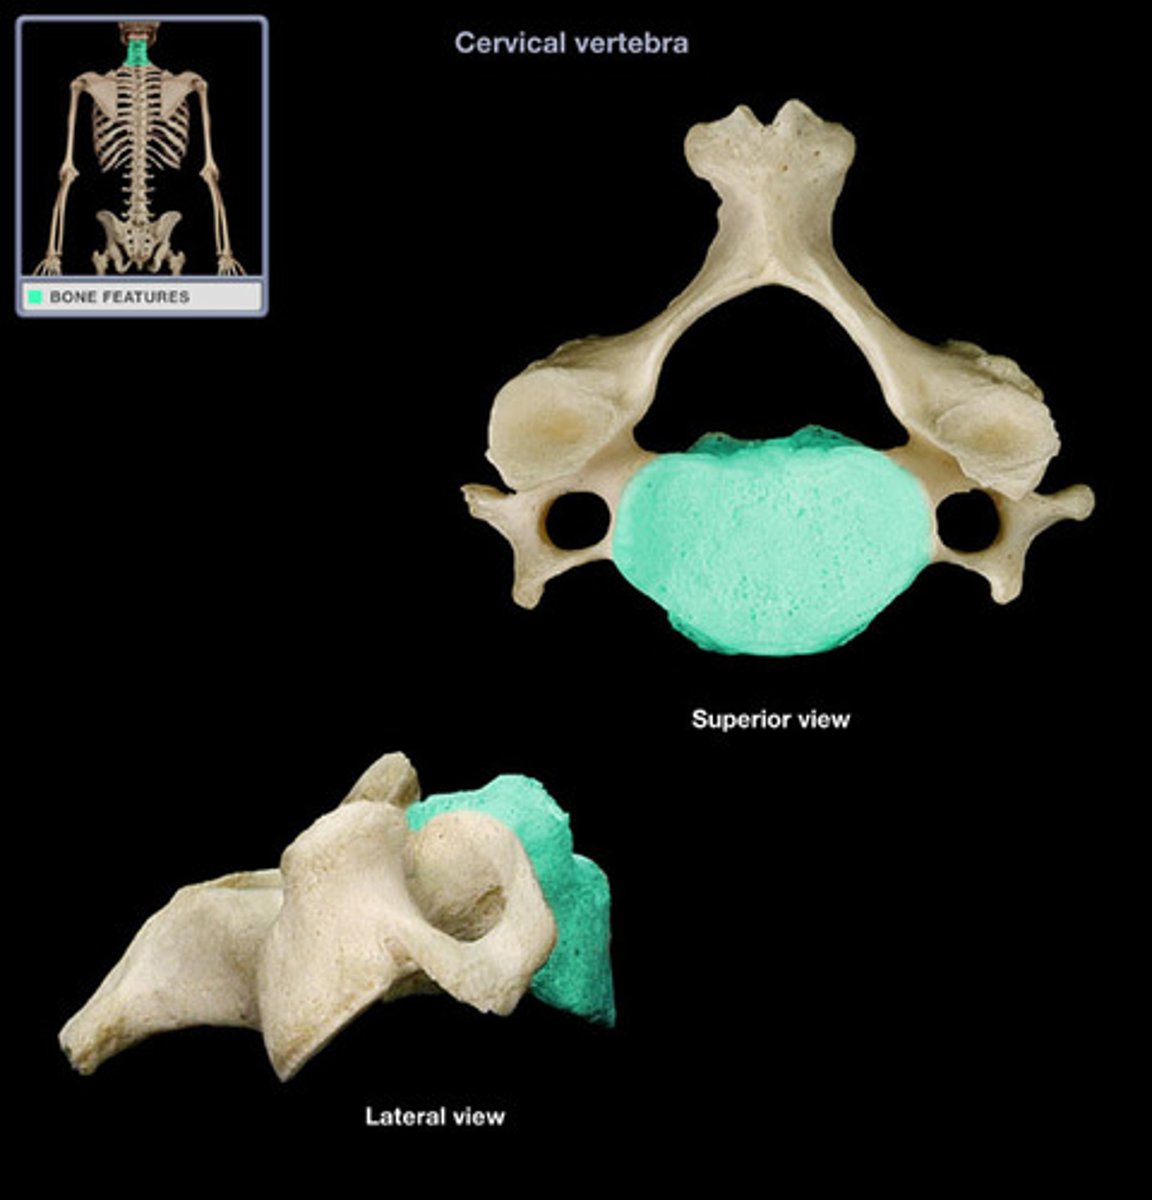

transverse formen (cervical)

the transverse formean (where vertebral artery passes thru)

what structure is the distingushing feature of the cervical vertebra

vertebral foramen

what structure is where the spinal cord passes thru

7 (C1-C7)

how many transverse foramen are there